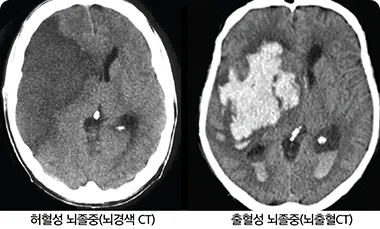

뇌혈관이 막히거나 터지는 질환을 부르는게 뇌졸중이고 그 중 뇌혈관이 막히는게 뇌경색 그리고 뇌혈관이 터지는 것을 뇌출혈이라고 합니다. 뇌졸중은 영구적인 손상이 많다고 하며 증상에 따라 전신이나 육체 일부 기능이 마비되는 등의 극심한 후유증이 남는 무서운 질병입니다 오늘은 뇌경색 초기증상에 대하여 알려드리도록 하겠습니다.